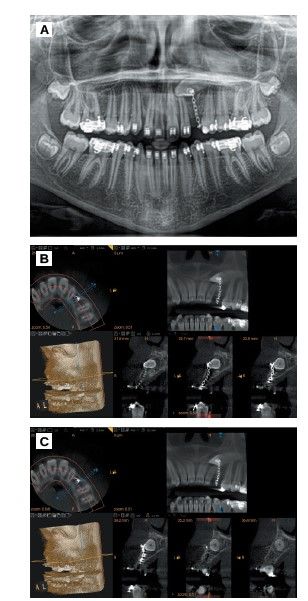

Measurements were made with the CBCT to determine the exact dimensions of the canine and the receiving area to ensure that the space was correct and was not necessary to modify it with orthodontics. In addition, anatomical relationships with adjacent structures were evaluated to avoid possible complications during surgery (Figure 1).

After a follow-up of 12 months, the brackets were removed. The patient was asymptomatic and the canine did not feel mobility or any pathology signs to clinical and radiographic examination (Figures 4A, 4B, 4C). Finally a crown elongation was performed to level the gingival margin to the contralateral canine. A guided surgery splint was planned, based on a previous digital waxing, which marked the position of both the new gingival margin and the bone level (Figures 4D, 4E, 4F).